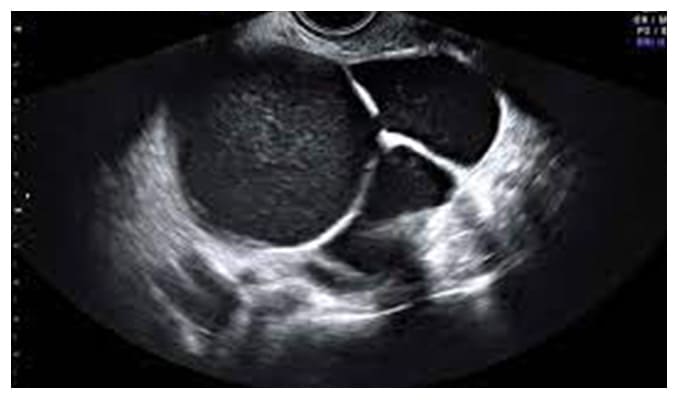

Los quistes de ovario son tumoraciones de contenido líquido, contenido dentro de los ovarios, pueden ser de "agua", "moco" o "sangre" dependiendo del tipo de quiste que se presente y en algunos casos puede ser mixto (contenido líquido y sólido) como los teratomas.

En especial en los quistes que tienen sangre (endometriomas) ya que la endometriosis es una enfermedad que daña la calidad y cantidad de los óvulos, ademas de otras alteraciones que son comentadas en el apartado de endometriosis.

Quistes de Ovario